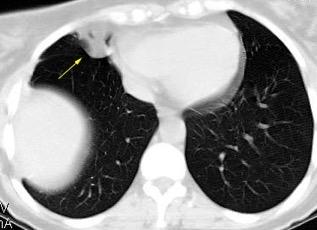

Signos radiológicos TC

Hallifax RJ et al. State-of-the-art: Radiological investigation of pleural disease Respiratory Medicine 2017

Nivel hidroaéreo o burbujas

Forma lenticular o elíptica Ángulos obtusos

> Grasa Extrapleural (60-80%)

Situación no gravitacional (no siempre)

Compresión de estructuras pulmonares

Límite muy bien definido Tabicación

Engrosamiento de la pleura parietal 36/ 59 exudados (61%) 56% de D. paraneumónicos 100% de empiemas Especificidad.. 96%.

Exudado versus trasudado.

Aquino SL, et al. Pleural exudates and transudates: diagnosis with contrast-enhanced CT. Radiology 1994

Signo de la Pleura separada “Split pleural sign”

Capas pleurales de grosor uniforme realzadas por el contraste

No específico de empiema. Indica “exudado”. 68% de pacientes con empiema pleural.

Capas pleurales de grosor uniforme

Realce grasa extrapleural (30%)

> Grasa Extrapleural. (60-80%)

Kraus GJ. Split pleural sign. Radiology 2007